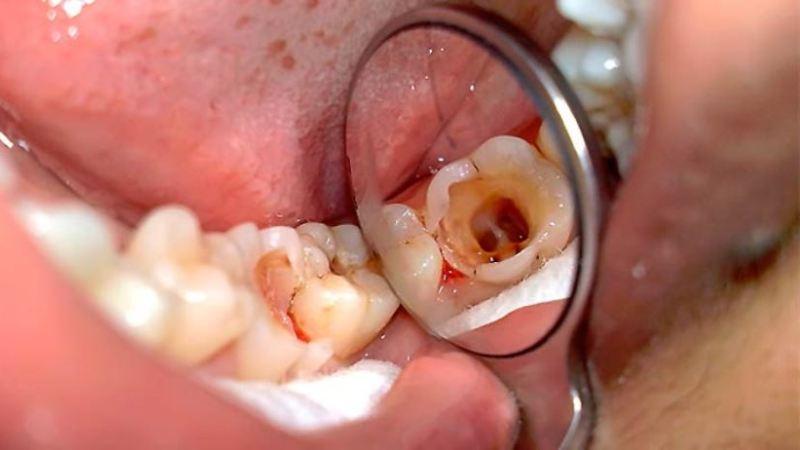

Хронический гангренозный тип заболевания

Хронический гангренозный пульпит проявляется у пациента интенсивными болевыми ощущениями, которые чаще всего возникают при употреблении горячей пищи или напитков.

Боли могут быть длительными и очень сильными. Они могут возникать спонтанно, особенно в вечерние и ночные часы.

Лечение включает в себя пломбирование затронутой области. В некоторых случаях наблюдается, что кариозный процесс затрагивает не один, а несколько соседних зубов. Это связано с распространением воспалительного процесса. Поэтому при первых признаках заболевания рекомендуется незамедлительно обратиться к стоматологу за консультацией.